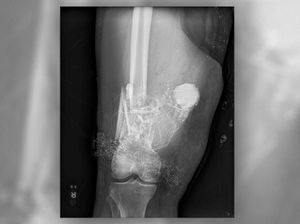

Menopause dini tidak hanya berpengaruh pada kehidupan seksual dan reproduksi. Kesehatan tulang juga terpengaruh, karena bikin tulang jadi mudah patah.